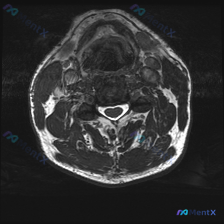

这张颈椎MRI能看到椎间盘病变吗?来看看分析思路

刚整理了一份很有启发的颈椎MRI读片病例,核心问题是“这张图里能观察到椎间盘病变吗?”,把完整分析思路分享给大家。

这是一张颈椎MRI轴位T2加权图像,我们先把观察到的结构特征理清楚:

- 椎体与椎管:脑脊液呈高信号,脊髓居中,形态规整,内部没有明显异常信号(无水肿灶);椎体后缘有轻微骨质增生,轻度向椎管内突起,但没有造成脊髓压迫变形。

- 附件结构:双侧小关节突轻度骨质增生,关节间隙稍狭窄,信号不均匀,黄韧带没有明显肥厚。

- 椎旁软组织:颈部深层肌肉信号正常,没有脂肪变性或水肿;颈前咽喉、气道结构清晰,层次正常。

- 椎间盘与神经结构:椎间盘没有明显向后突出压迫硬膜囊,椎间隙高度基本正常;双侧椎间孔形态尚可,没有明显骨性狭窄压迫神经根;没有发现肿块、脓肿或淋巴结肿大。